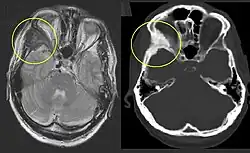

On x-ray, fibrous dysplasia appears as bubbly lytic lesions, or a ground glass appearance. Computerized tomography (CT) or magnetic resonance imaging (MRI) scans may be used to determine how extensively bones are affected. CT can better demonstrate the typical "ground glass" appearance, which is a highly specific radiological finding, while MRI can show cystic areas with fluid contents.[15] A bone scan uses radioactive tracers, which are injected into your bloodstream. The damaged parts of bones take up more of the tracer, which show up more brightly on the scan. A biopsy, which uses a hollow needle to remove a small piece of the affected bone for laboratory analysis, can diagnose fibrous dysplasia definitely.